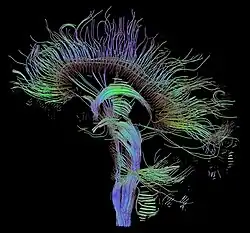

Medicine has been practiced since prehistoric times, and for most of this time it was an art (an area of creativity and skill), frequently having connections to the religious and philosophical beliefs of local culture. For example, a medicine man would apply herbs and say prayers for healing, or an ancient philosopher and physician would apply bloodletting according to the theories of humorism. In recent centuries, since the advent of modern science, most medicine has become a combination of art and science (both basic and applied, under the umbrella of medical science). For example, while stitching technique for sutures is an art learned through practice, knowledge of what happens at the cellular and molecular level in the tissues being stitched arises through science.